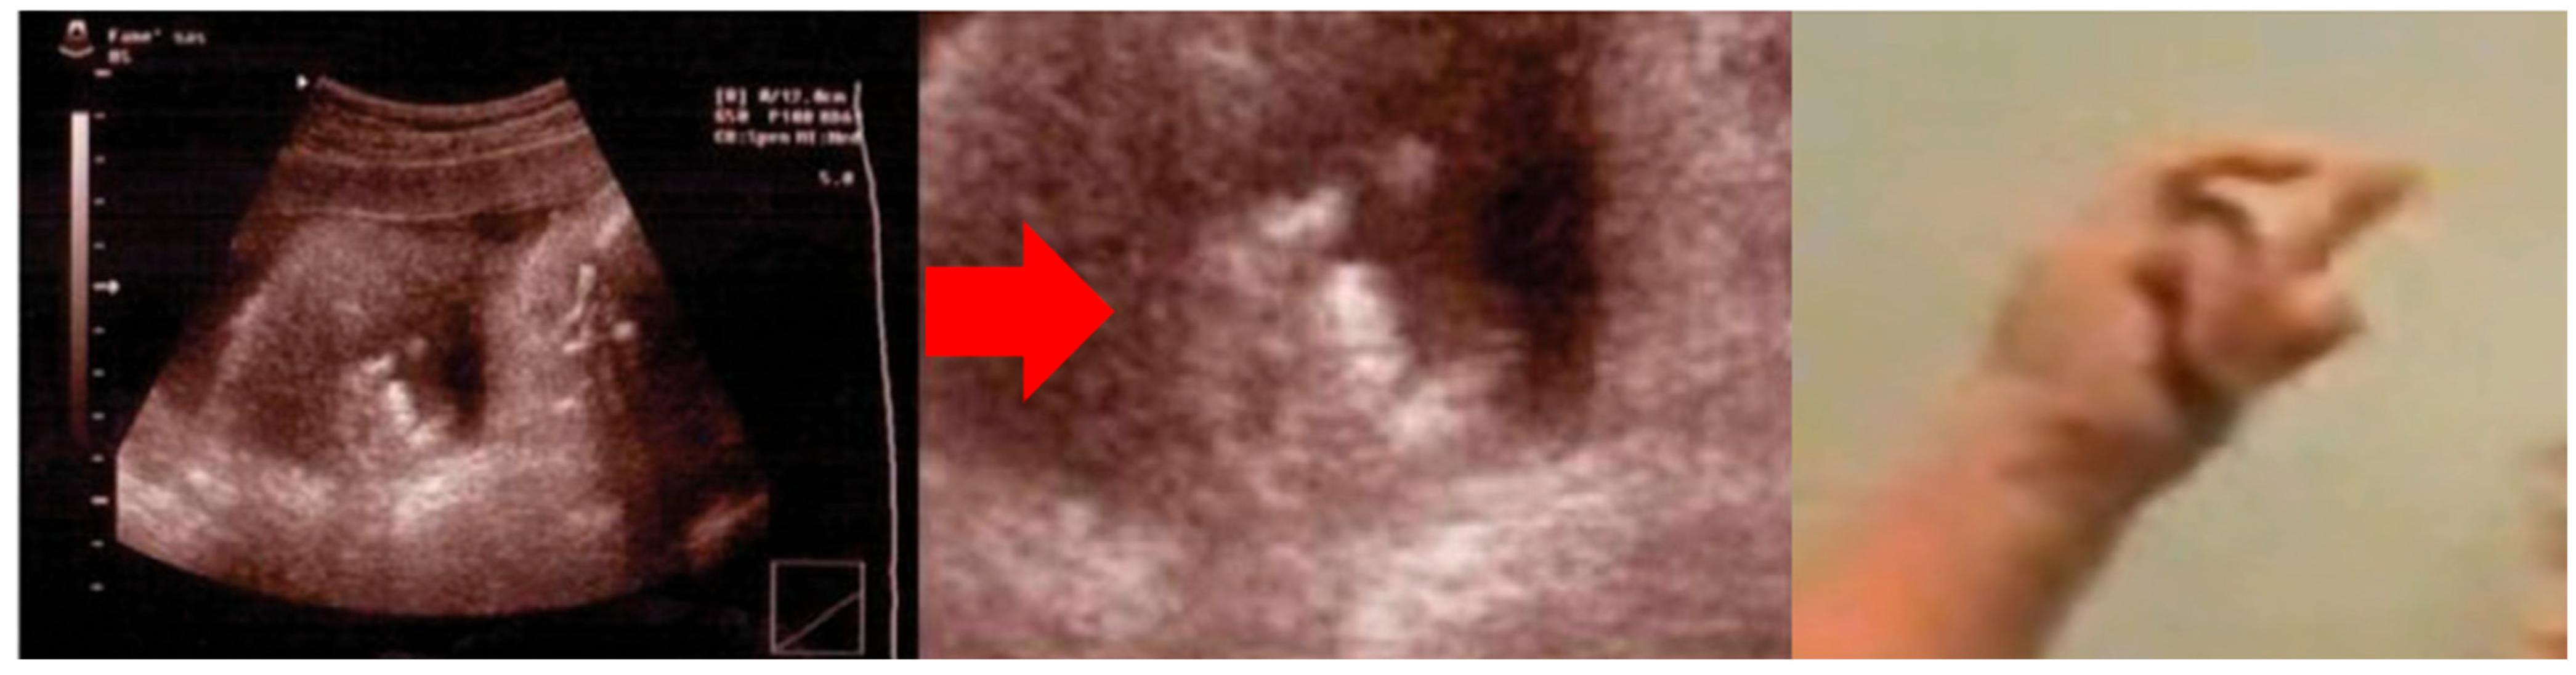

- Dessì, A.; Fanos, V.; Crisponi, G.; Frau, A.; Ottonello, G. Isolated ‘sign of the horns’: A simple, pathognomonic, prenatal sonographic marker of Crisponi syndrome. J. Obstet. Gynaecol. Res. 2012, 38, 582–585. [Google Scholar] [CrossRef] [PubMed]

| Evidence prompting suspicion of cs/ciss | Orofacial muscle contractions, generalized paroxysmal events, camptodactyly | Prenatal bilateral camptodactyly |